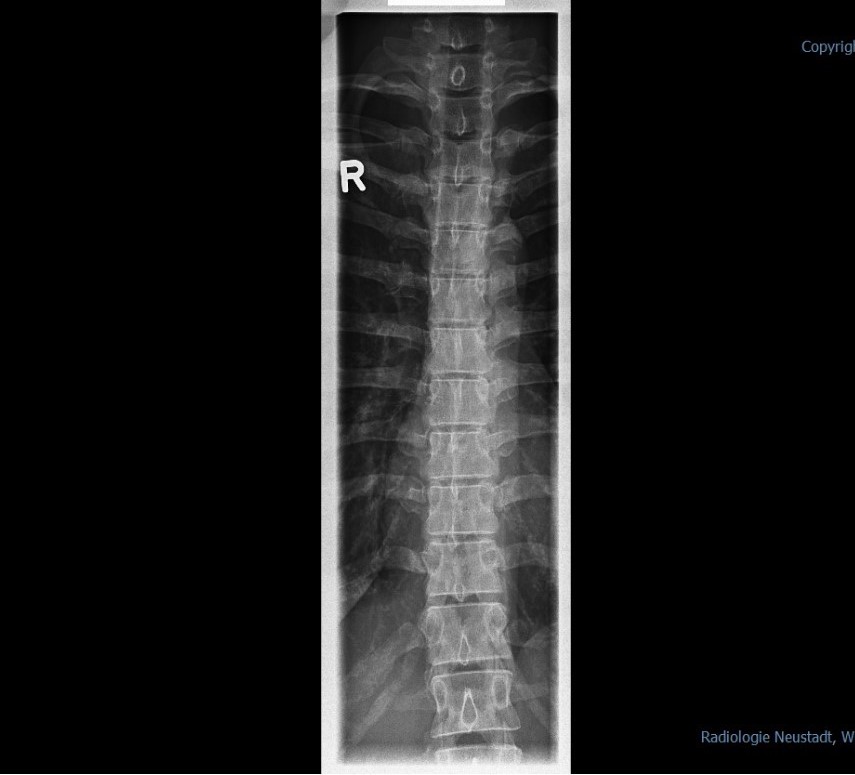

Ich hoffe ich habe alles erwähnt. Was soll ich tun? was meint und empfehlt ihr mir? Ich habe die Röntgenbilder mit eingefügt.

1.jpg

(113.68 KiB) Noch nie heruntergeladen

Zuerstmal bin ich irritiert, weil ich nicht verstehe, wie ein Arzt bei der Wirbelsäule von einer Skoliose sprechen kann. Von einer Skoliose spricht man erst ab 20°, und das sind vielleicht gerade mal 5°, so wie ich das schätze. Ich bin, wie gesagt, kein Fachmann, und ich konnte nur eine der beiden Dateien öffnen, aber das scheint mir falscher Alarm zu sein. ;)